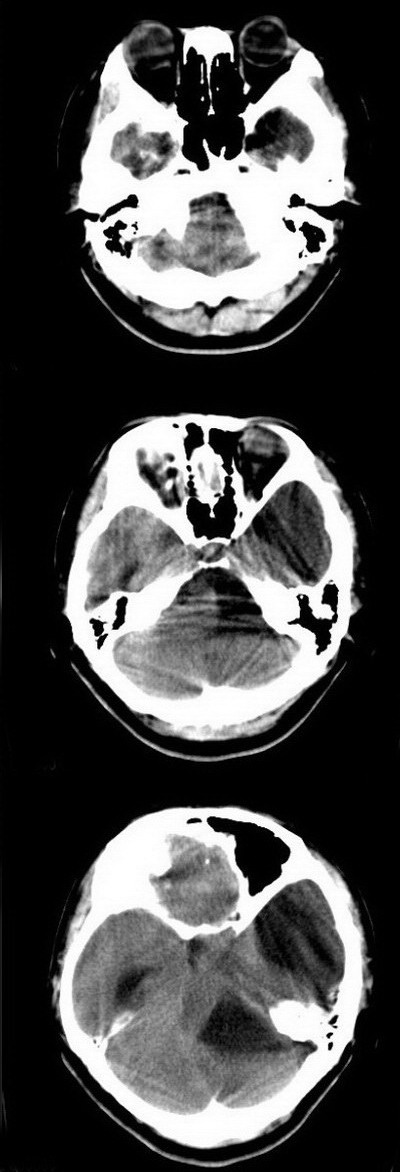

标题: CT16833:F34Y,左侧积水型无脑畸形?请指教. [打印本页]

标题: CT16833:F34Y,左侧积水型无脑畸形?请指教.

女.34.自幼右下肢跛行.智力正常,未发现其它不适。

本例视间隔缺如,基底灰质核团移位,左侧大脑实质较多,能活到这么大还智力正常,多考虑大脑发育不良伴脑积水,积水型无脑畸形一般实质较少而且活不大,智力低下

左侧脑裂畸形(完全型、分离型)。

脑裂畸形基本改变为横贯大脑半球的裂隙,其外端的软脑膜与内端的室管膜通过裂隙相连接,形成软脑膜—室管膜缝(p-e缝)。分离型裂隙在ct上可清晰显现,不难诊断。融合型裂隙,在ct上则易漏诊。但如发现横贯大脑半球的与灰质密度相同的带状影,其外端脑表面出现凹陷,内端脑室呈现天幕状憩室,即可作出正确诊断。

考虑脑穿通畸形伴脑积水。